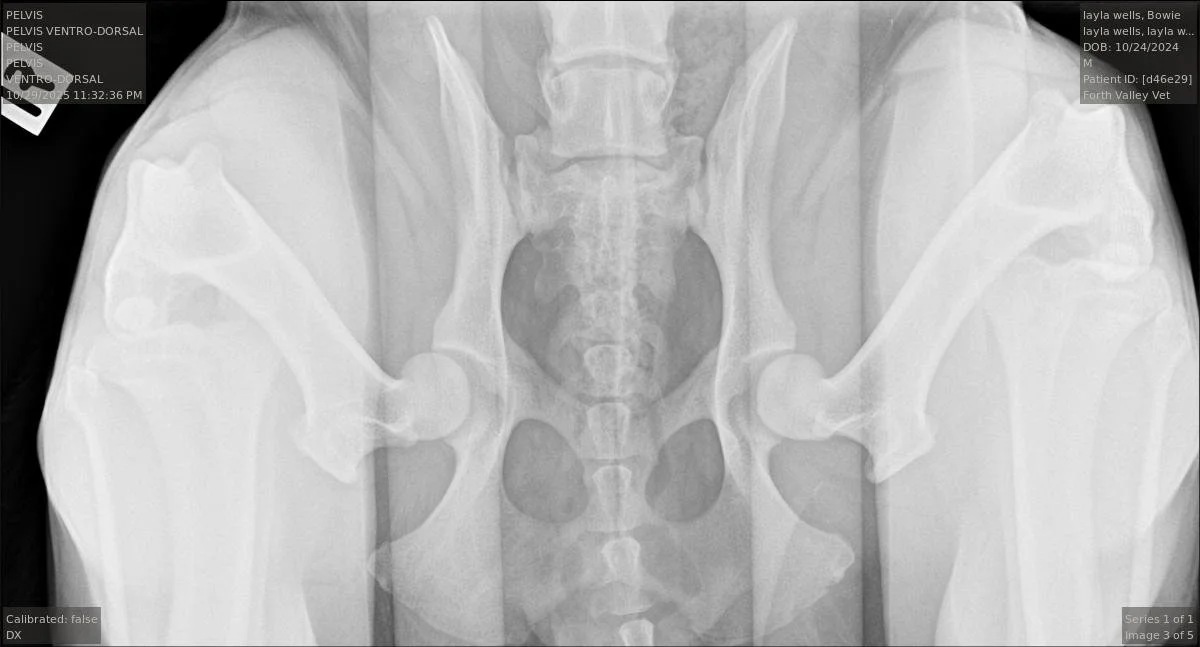

The Distraction View: To measure maximum laxity.

The PennHIP method uses a specialized device to gently stress the joint while the dog is anaesthetised, measuring exactly how much the hip ball can move away from the socket. This gives us a Distraction Index (DI) score.